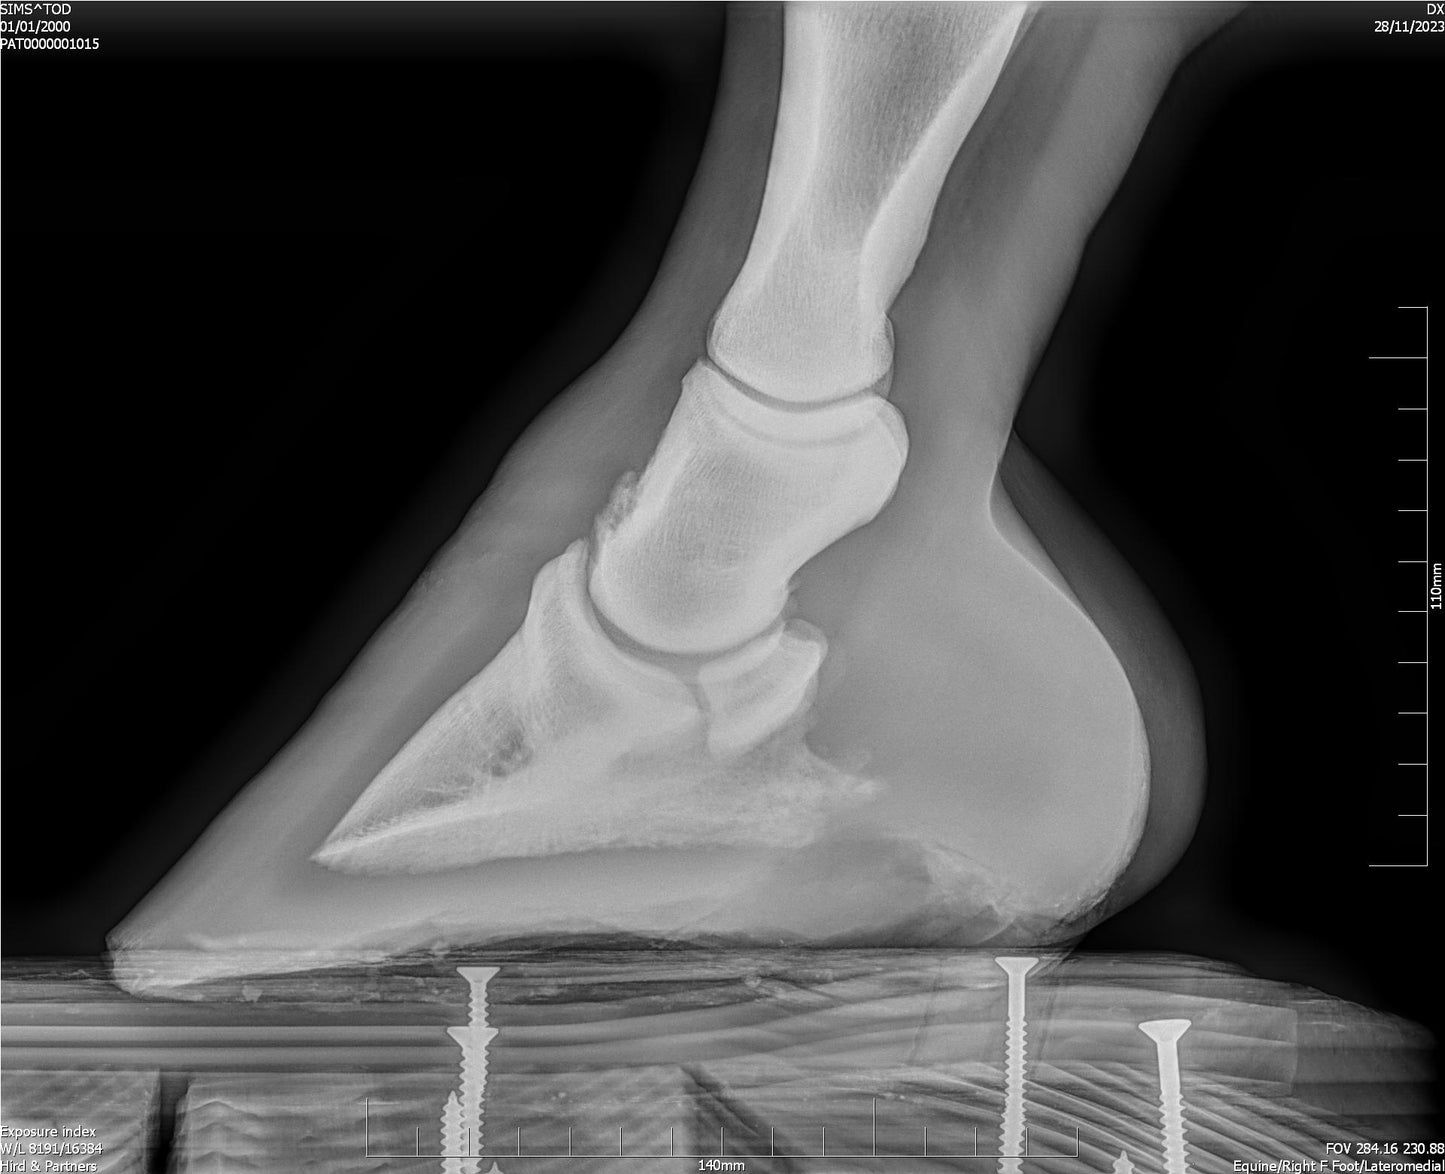

X-ray imaging, on the other hand, is primarily used to assess bone health and identify fractures, arthritis, or other skeletal conditions.